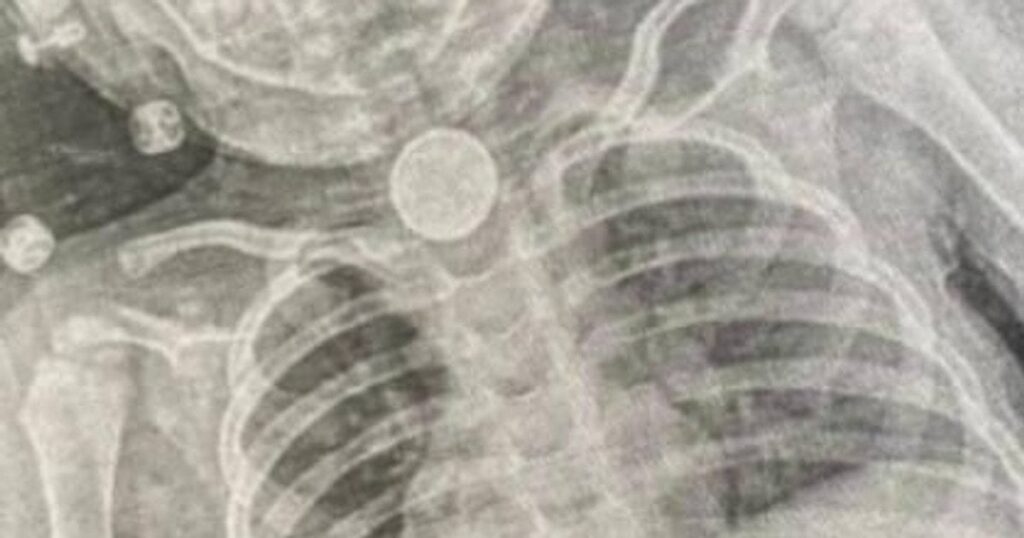

Ситуація почала погіршуватися навесні. Коли у Софійки з’явилися блювання, свистяче дихання та повна відмова від їжі, рентген-знімок нарешті підтвердив наявність стороннього предмета. Медики з’ясували, що батарейка діаметром 2,5 см щільно застрягла в першому фізіологічному звуженні стравоходу, спричинивши набряк та пошкодження слизової оболонки.